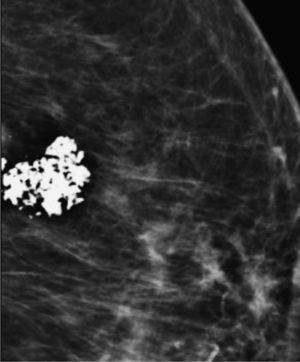

Fibroadenoma calcificado (fig. 7). Los fibroadenomas son lesiones frecuentes en mujeres jóvenes. En la menopausia tienden a involucionar y en fases más tardías la hialinización del fibroadenoma suele formar calcificaciones típicas, grandes y groseras (en forma de palomita de maíz)1-3.